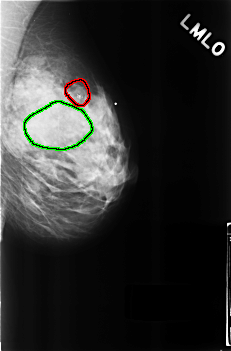

C_0272_1.RIGHT_CC

LEFT_MLO LINES 4560 PIXELS_PER_LINE 2992 BITS_PER_PIXEL 12 RESOLUTION 50 OVERLAY

FILE: C_0272_1.LEFT_MLO.OVERLAY

TOTAL_ABNORMALITIES 2

ABNORMALITY 1

LESION_TYPE CALCIFICATION TYPE AMORPHOUS DISTRIBUTION CLUSTERED

ASSESSMENT 4

SUBTLETY 5

PATHOLOGY BENIGN

TOTAL_OUTLINES 1

BOUNDARY

ABNORMALITY 2

LESION_TYPE MASS SHAPE OVAL MARGINS OBSCURED

ASSESSMENT 3

SUBTLETY 4